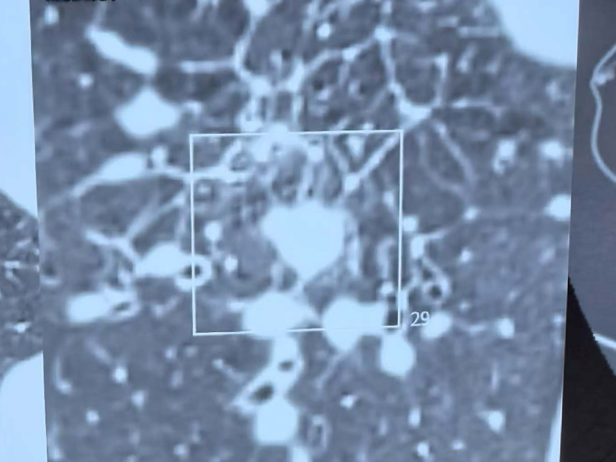

在麻醉团队的全力保障下,陶冀教授团队凭借丰富的临床经验和精湛的技术,采取左侧卧位,运用单针精准分段穿刺技术,如同一位技艺高超的工匠,将消融针尖精准无误地置入病灶核心。术中,他们以30—40W的中低功率进行消融,持续9分钟后,谨慎退针并补充消融,通过两个精心设计的消融循环,确保消融范围完全覆盖病灶,实现肿瘤的彻底灭活。手术过程顺利,术中无出血,仅出现少量气胸,经置管抽气后迅速缓解,重要血管与支气管均得到妥善保护。